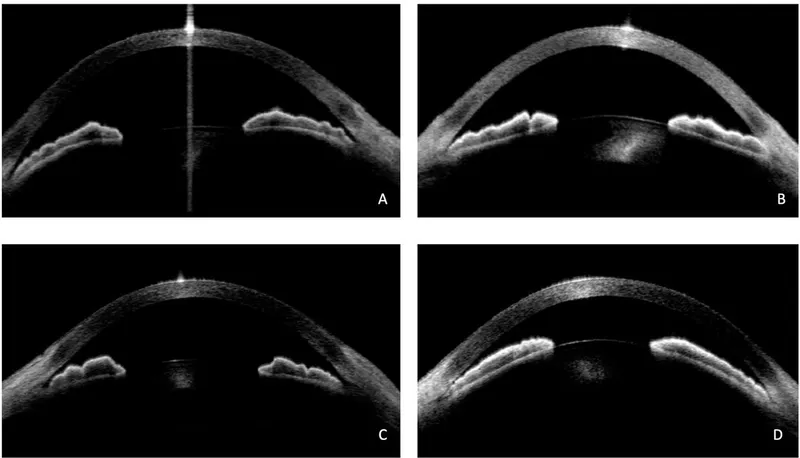

- Ultrasound Biomicroscopy (UBM): Visualizes angle structures if cornea hazy; ciliary body assessment.